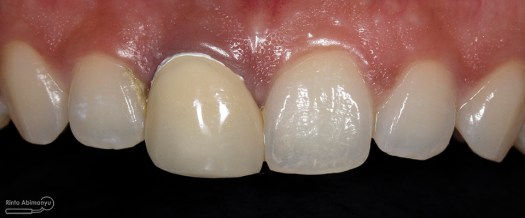

Foto klinis setelah pemasangan crown

“waah…. bagus doook…” ucap pasien pas diberikan kaca untuk melihat hasilnya

Alhamdulillah ekspektasi pasien terpenuhi dan ini yang tidak bisa dinilai dengan apapun, kita sebagai operator rasanya tuh bahagia banget… iya gak sih? apa gue yang lebay ya hahaha 😀